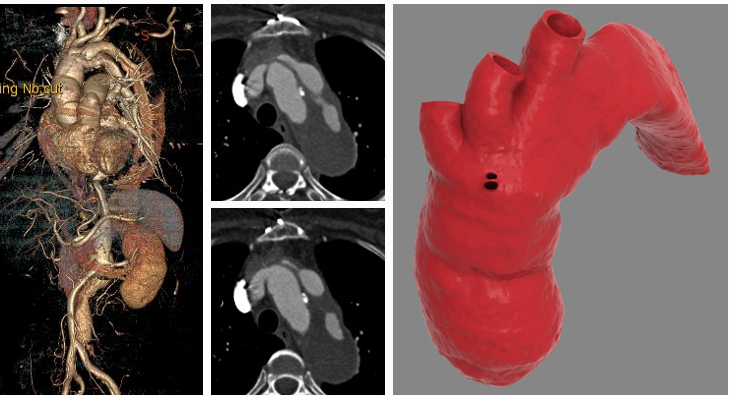

★ 其他技术

1. 假腔栓塞技术

2. 杂交手术:开窗/分支支架重建内脏动脉

3. 平行支架技术

4. 覆膜支架技术

5. 逆向分支技术

6. 3D打印辅助开窗技术

7. G-Branch支架系统:多分支一体化重建内脏动脉

8. VSD封堵伞封堵破口